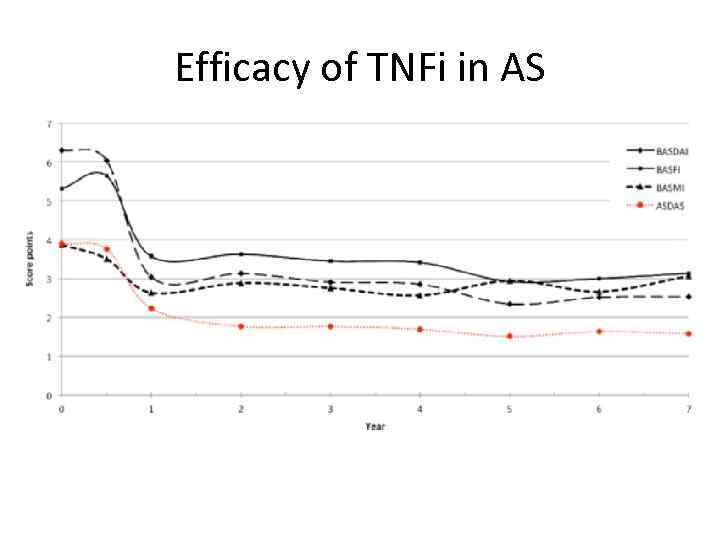

Efficacy of TNFi in AS